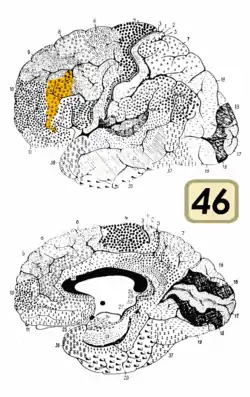

Brodmann area 46

Brodmann area 46, or BA46, is part of the frontal cortex in the human brain. It is between BA10 and BA45.

BA46 is known as middle frontal area 46. In the human brain it occupies approximately the middle third of the middle frontal gyrus and the most rostral portion of the inferior frontal gyrus. Brodmann area 46 roughly corresponds with the dorsolateral prefrontal cortex (DLPFC), although the borders of area 46 are based on cytoarchitecture rather than function. The DLPFC also encompasses part of granular frontal area 9, directly adjacent on the dorsal surface of the cortex.

Cytoarchitecturally, BA46 is bounded dorsally by the granular frontal area 9, rostroventrally by the frontopolar area 10 and caudally by the triangular area 45 (Brodmann-1909). There is some discrepancy between the extent of BA8 (Brodmann-1905) and the same area as described by Walker (1940).[1]

Lateral view.